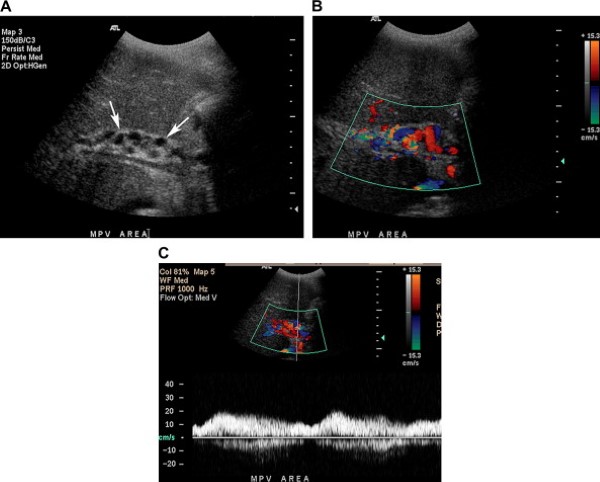

Các tĩnh mạch gan phải, tĩnh mạch gan giữa và tĩnh mạch gan trái và hợp lưu của chúng có thể nhìn thấy rõ bằng siêu âm dưới dạng các cấu trúc ống không có thành và dòng chảy đi xa đầu dò, rồi đổ về tĩnh mạch chủ dưới [1]. Tĩnh mạch gan giữa ngăn cách các thùy gan phải và thùy gan trái, chạy giữa phân thùy trước của thùy gan phải và phân thùy giữa của thùy gan trái. Tĩnh mạch gan phải nằm giữa phân thùy trước và phân thùy sau của thùy gan phải, và tĩnh mạch gan trái chạy giữa phân thùy giữa và phân thùy bên của thùy gan trái. Nhịp đập từ tim phải phản hồi đến sóng của các tĩnh mạch gan, với dạng sóng ba pha bao gồm hai thì dòng chảy xuôi tương ứng với thì tâm trương nhĩ và thì tâm thu thất [2]. Giai đoạn đảo ngược dòng chảy tạm thời tương ứng với co tim phải trong thì tâm thu nhĩ (Hình 4) [1].

Hình 4. Các tĩnh mạch gan bình thường. (A) Ảnh siêu âm thang xám cho thấy hợp lưu của cả ba tĩnh mạch gan đổ vào tĩnh mạch chủ dưới. (B) Ảnh Triplex Doppler cho thấy dòng chảy ba pha ở tĩnh mạch gan giữa.

Hình 5. Dòng chảy hai chu chuyển vòng ở tĩnh mạch cửa bệnh nhân nữ 59 tuổi có tiền sử suy tim phải và viêm gan C. (Hình A) Ảnh siêu âm Doppler màu chứng minh dòng chảy hai chu chuyển vòng trong tĩnh mạch cửa, sóng kéo dài ở trên và dưới đường cơ bản. (Hình B) Ảnh siêu âm thang xám phát hiện các tĩnh mạch gan giãn to đổ về tĩnh mạch chủ dưới cũng bị giãn (các mũi tên) do suy tim phải và tăng thể tích tuần hoàn. (Hình C) Sóng mạch đập mạnh ở bên trong tĩnh mạch gan giữa.

Sóng mạch đập nhẹ ở tĩnh mạch có thể gặp trong các trường hợp biến đổi bình thường, đặc biệt ở những người trẻ tuổi và gầy (Hình 6).

Hình 6. Dòng chảy bình thường, đập nhẹ ở tĩnh mạch cửa bệnh nhân nữ 35 tuổi đau sườn phải.